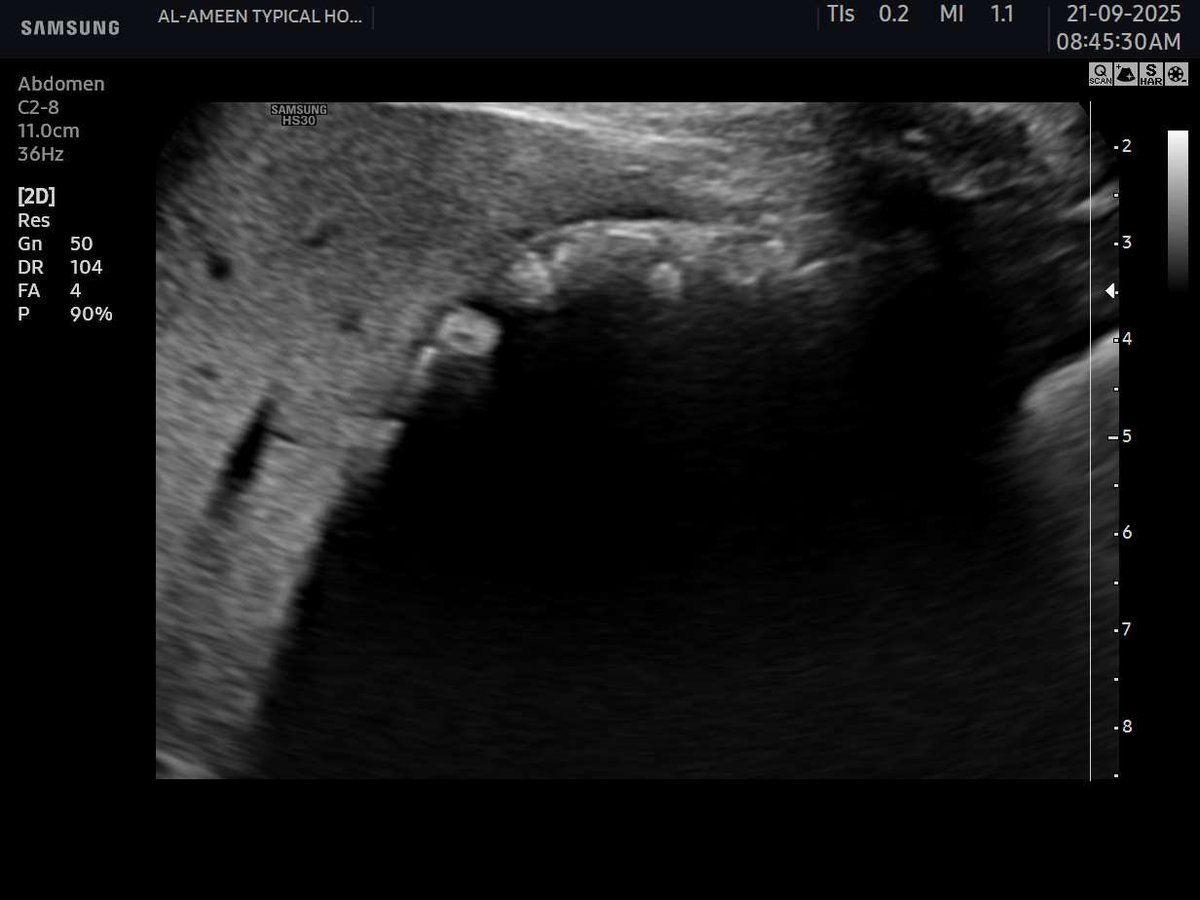

This 50 years female pt came with acute pain in the epigastrium and jaundice. Your opinion? Name of the sonographic sign?? Area of scan :RUQ. #EchoTech

This 50 years female pt came with acute pain in the epigastrium and jaundice. Your opinion? Name of the sonographic sign?? Area of scan :RUQ. #EchoTech